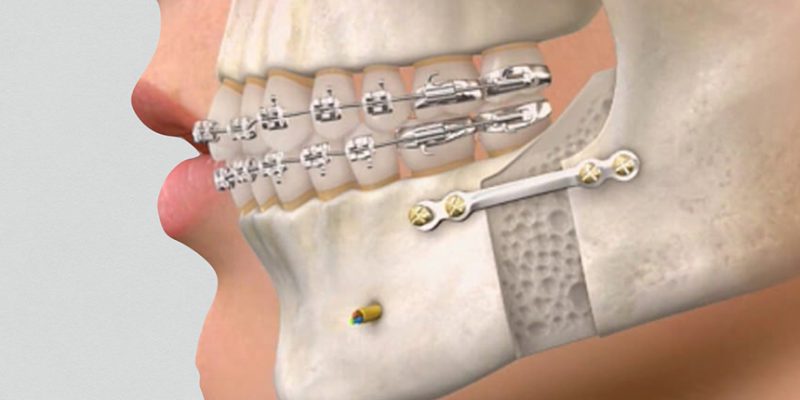

Nossa equipe de cirurgiões bucomaxilofaciais está equipada para tratar uma variedade de condições, desde extrações dentárias complicadas até cirurgias de correção facial. Se você precisa de remoção de dentes impactados, realinhamento da mandíbula ou tratamento de lesões e deformidades faciais, nossos especialistas têm a experiência e a habilidade para oferecer soluções eficazes e restauradoras.